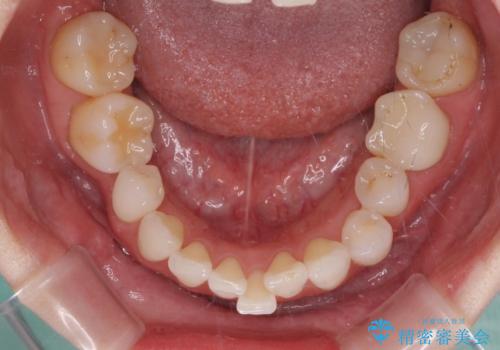

- 上下前歯のデコボコと奥歯の欠損を気にして来院された患者様です。

右下の欠損分は奥歯が倒れ込んでスペースがなくなっていたため、矯正治療により本来の位置に歯を移動させ、オールセラミックブリッジによる欠損補綴治療を行うこととしました。

右下は移動量が多いため、十分な移動が達成されない場合はワイヤー装置を使用する予定としておりましたが、しっかりとマウスピースを装着してくださったため、前歯とともに十分に歯を動かすことができました。